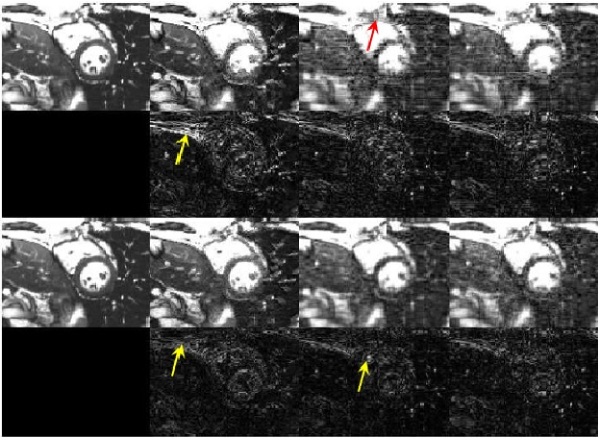

The random subsampling policy developed in Section V is tested here to sample Cartesian phase encoded lines for interpolation of missing -space data in dataset (D1). Since only the rows are selected, the score in (15) is marginalized over the columns to arrive at the modified score , and subsequently random trials are drawn with replacement to sample the rows. As before, the first five frames are fully acquired to serve as a warm subspace startup. Evolution of NMSE is depicted in Fig. 7 under -fold acceleration for the adaptive sampling scheme, and its non-adaptive counterpart using variable density sampling with parameters for the polynomial distribution . After dozen iterations the latent structure in -space data is gradually learned and as a result subspace-driven sampling starts outperforming the variable density sampling. This observation suggests that one better adopt variable density sampling with to pick the low frequency components for the early iterations to end up with a reliable subspace estimation, and then switch to adaptive subsampling for improved quality. The reconstructed frames at time are shown in Fig. 9, where one can confirm from the residual images that our novel scheme creates less artifacts as delineated by the arrows. For the resultant sampling patterns with temporal realizations, the sampling distribution for phase encoded lines is also depicted in Fig. 8.